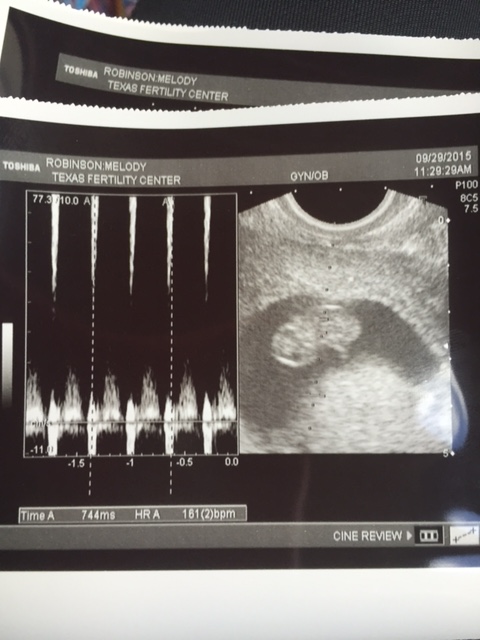

8 Weeks 5 days yesterday! HR-161 We tried to Ramzi the US and came up with nothing. Being transferred from our RE to an OB-GYN. Starting to really feel real now!